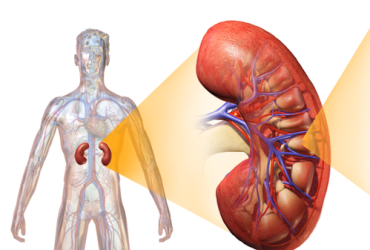

Uma nova modalidade de teste rápido para detecção de possíveis lesões ...